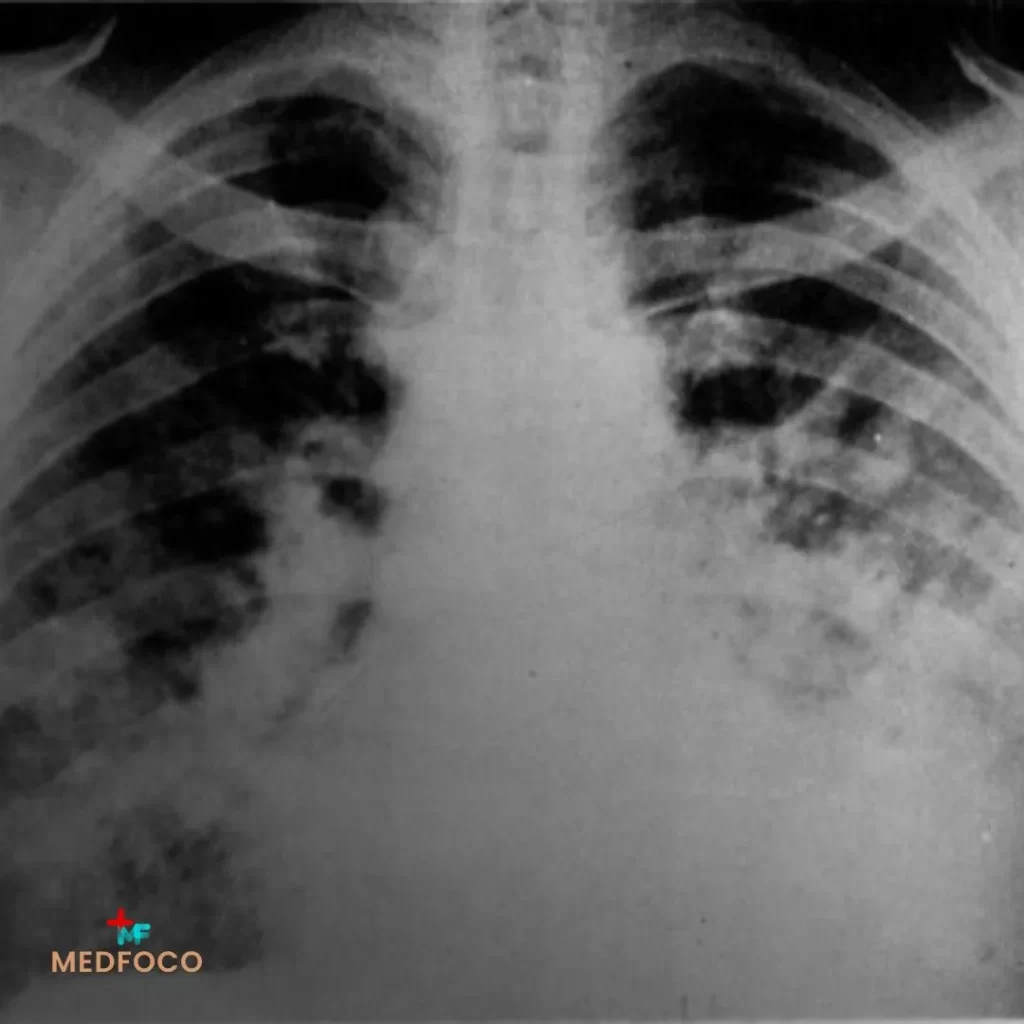

Tularemia pneumônica

Forma mais grave e potencialmente fatal

Ocorre pela inalação de aerossóis contaminados (ex. feno, grãos ou poeira com excretas de roedores), sendo considerada forma primária. Também pode surgir como complicação de outra forma clínica (disseminação hematogênica). Apresenta alto risco de sepse e mortalidade elevada sem tratamento precoce.

Sinais e sintomas:

- Tosse seca ou produtiva, às vezes com expectoração hemoptoica

- Dispneia e dor torácica pleurítica

- Febre alta e calafrios intensos

- Taquipneia, taquicardia e hipoxemia

- Infiltrado pulmonar localizado ou bilateral na radiografia/TC

- Radiografia/TC de tórax: infiltrados em formas pneumônicas